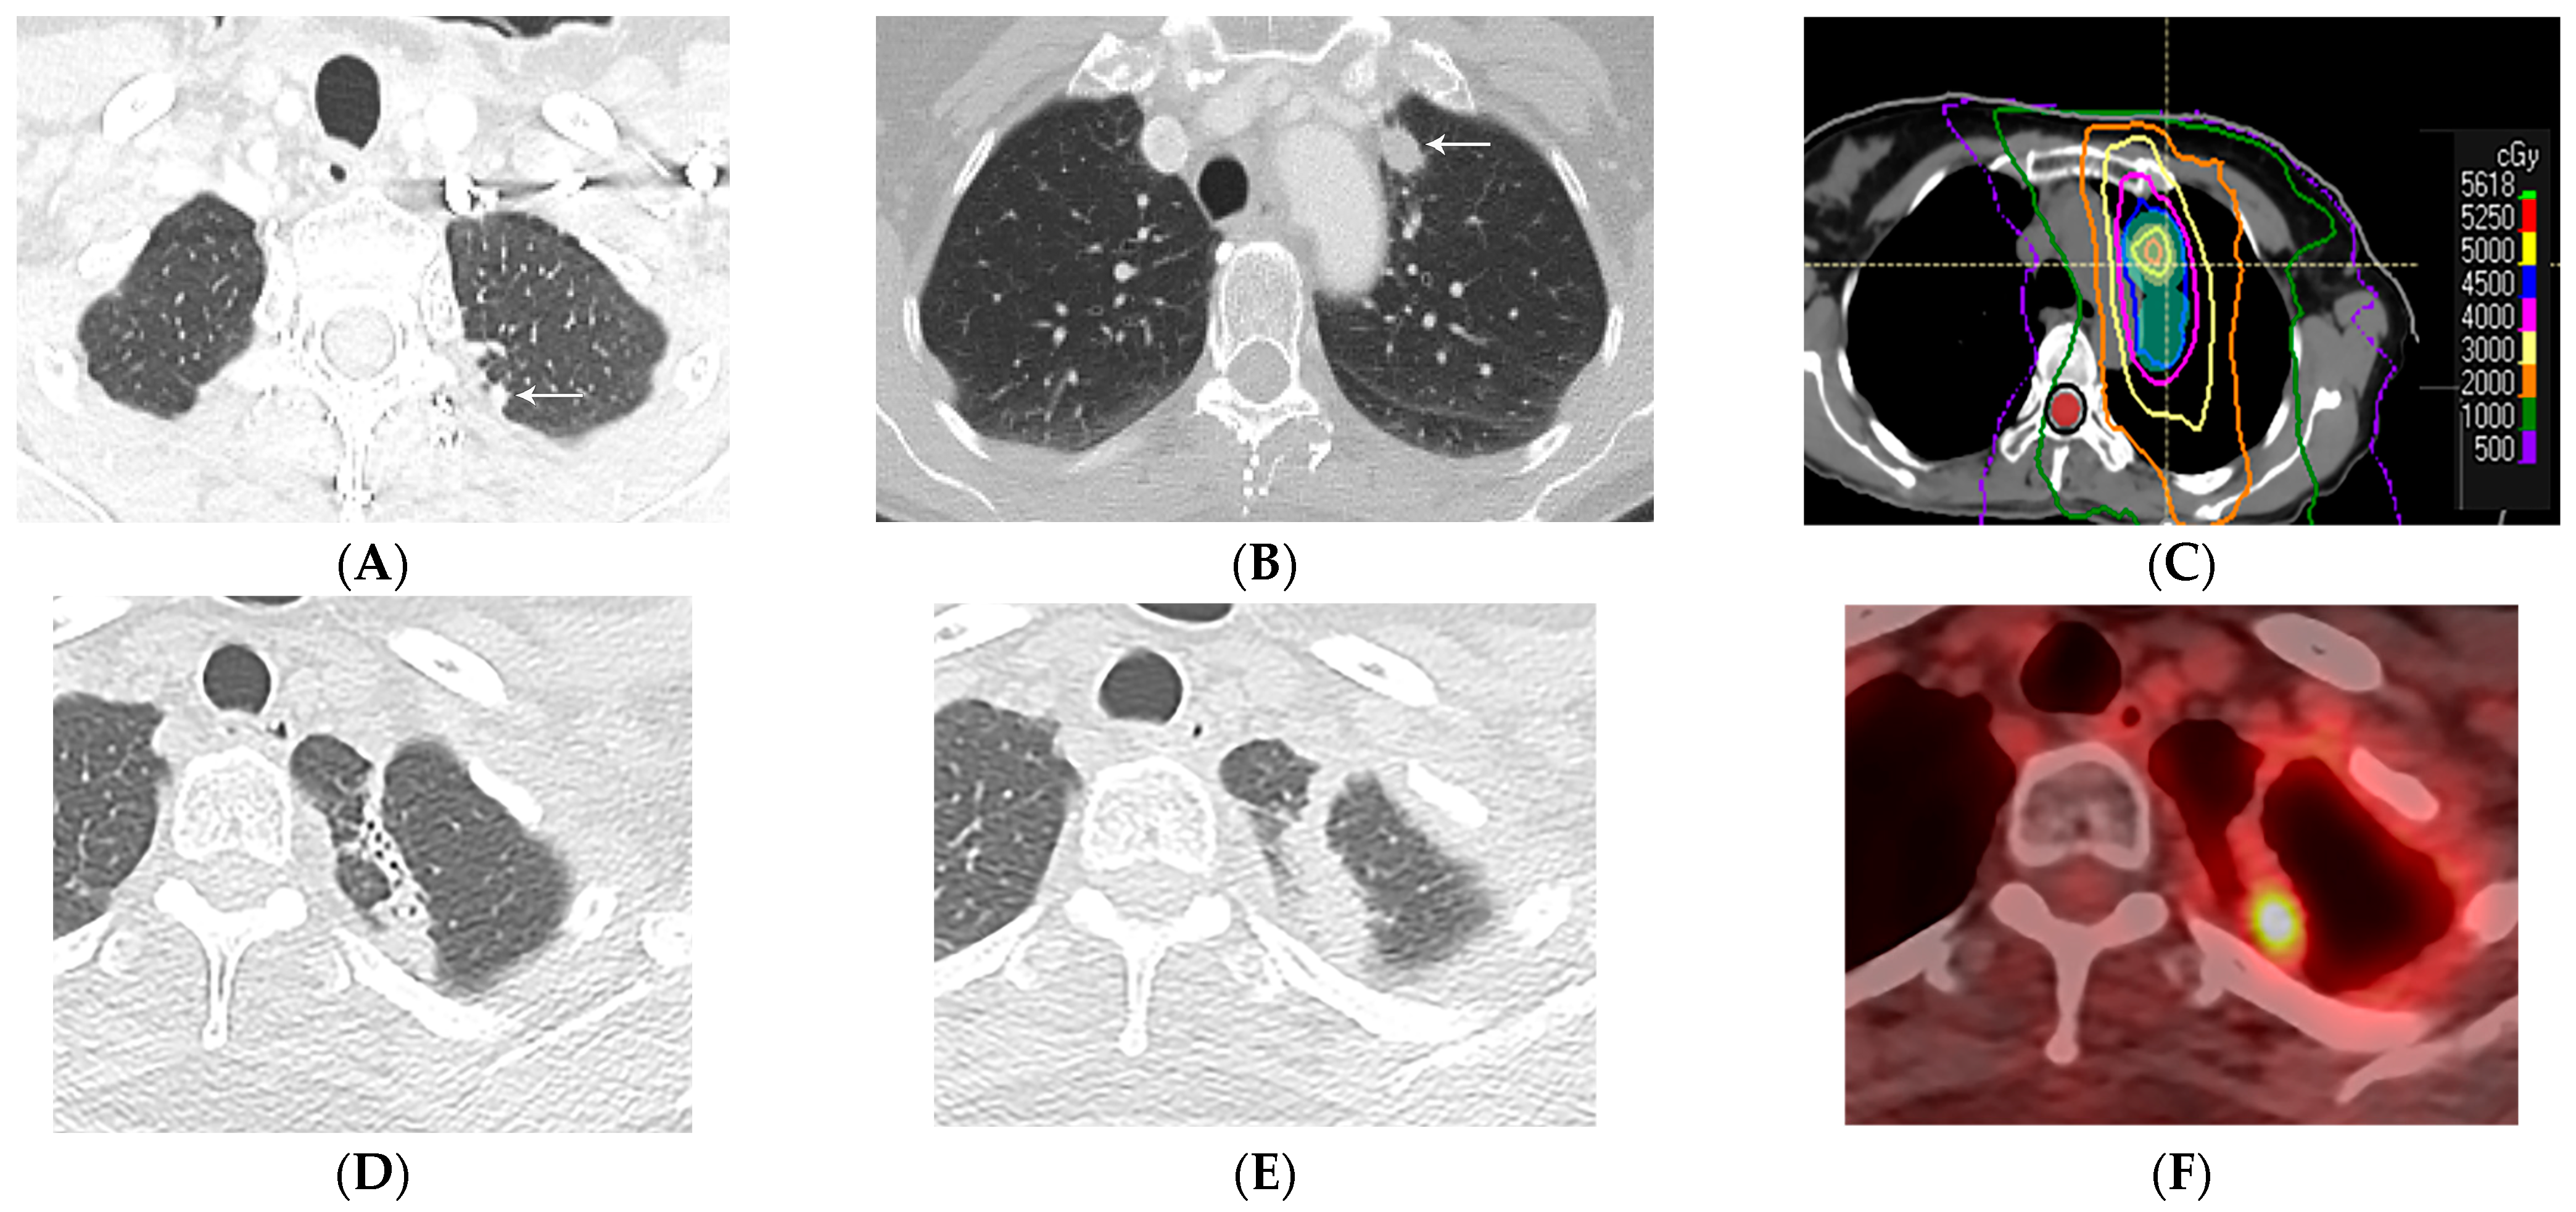

7.1. In Situ Pulmonary Artery Thrombosis